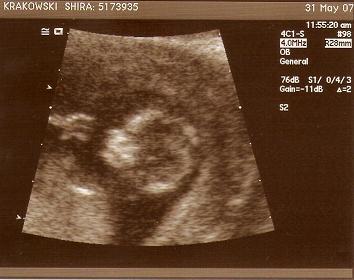

So here's a quick look at where we are - The first picture was taken on week #12. We could see both arms with fingers and both legs. That's already a good sign, isn't it? The 2 other pictures are from week 12. We could already see the fetus kicking and boxing. Apparently it is too small for Shira to feel anything for the moment.

Can you notice the face in the picture below? Can you tell if he/she looks like Shira or Oz??